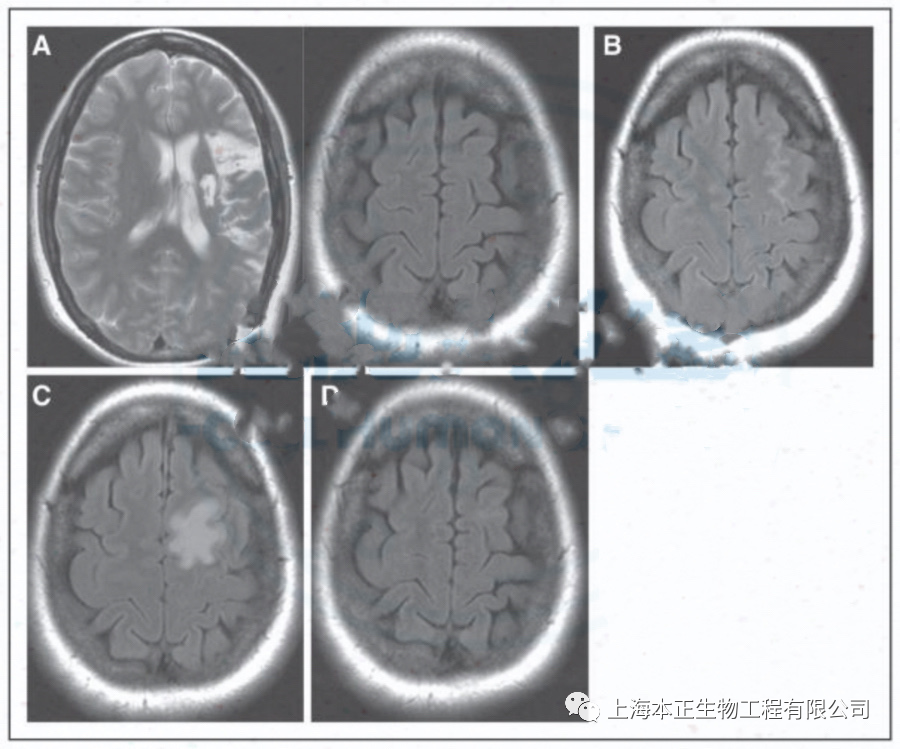

上面四幅图均为该研究中一名 39 岁女性患者的脑部共振扫描图,此名患者在左大脑中动脉中风 2 年后接受了干细胞治疗。

图A左侧显示移植前脑部出现皮质下和皮质梗死。右侧显示了在较高轴向水平的干细胞治疗范围;图B为治疗后第 1 天在较高轴向水平左额叶沟中有少量血液;图C为在较高轴向水平移植后第 7 天,脑区显示与运动前回相邻的左额上回出现新的 T2 FLAIR 信号异常;图D为治疗后第 2 个月在较高轴向水平显示 T2 FLAIR 异常信号消退。T2 FLAIR为核磁共振检查的描述,一般为水肿信号。